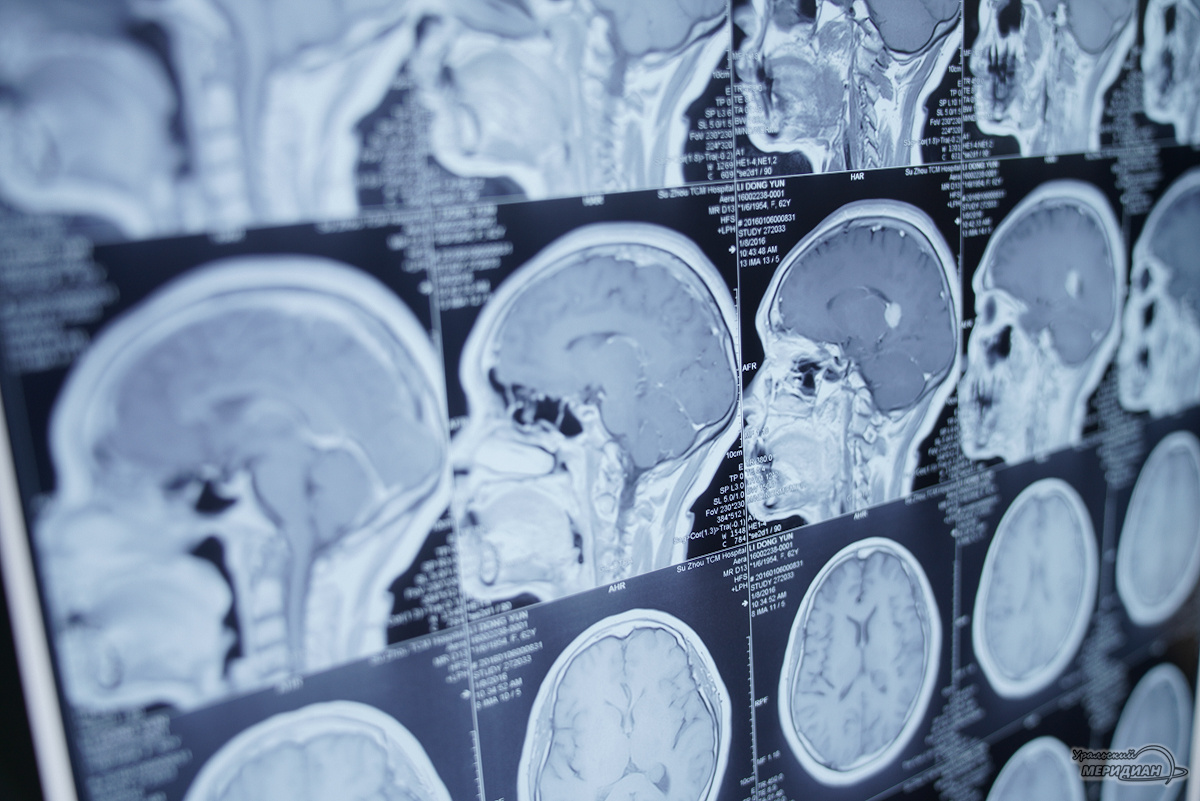

При поступлении в больницу врачи диагностировали у пациента перелом ключицы и черепно-мозговую травму с образованием стремительно растущей внутричерепной эпидуральной гематомы. Кроме того, молодой человек страдает хронической почечной недостаточностью и уже два года находился на гемодиализе.

Нейрохирург Михаил Усов пояснил, что операция по удалению гематомы у пациента с гемодиализом требует особого подхода, так как у таких больных ткани имеют повышенную кровоточивость. В ходе операции медики уделили особое внимание гемостазу для минимизации кровопотери и предотвращения осложнений. Хирургическое вмешательство прошло успешно благодаря слаженной работе операционной бригады и анестезиолога-реаниматолога Джулии Сумейковой.